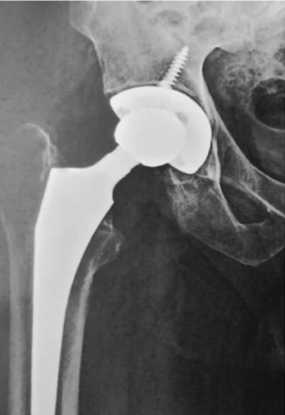

Перед оперативным лечением по назначению клинического фармаколога проведен курс комбинированной антибактериальной терапии: меропенем 2000 мг 3 раза в сут. в/в, амикацин 1000 мг 1 раз в сут. в/в в течение 15 дней. 27.03.2023 проведена резекция головки левой бедренной кости, установка артикулирующего двухслойного спейсера с гентамицином (4 г) (рис. 2). ПЦР операционного материала от 28.03.2023: ДНК микробактерии туберкулеза (МБТ) не обнаружена. Послеоперационный период протекал без осложнений.

Рис. 2. Рентгенограмма левого тазобедренного сустава пациента Ш. в первые сутки после операции по установке артикулирующего цементного спейсера с двухслойной головкой. Наружная цементная мантия содержит 4 г гентамицина